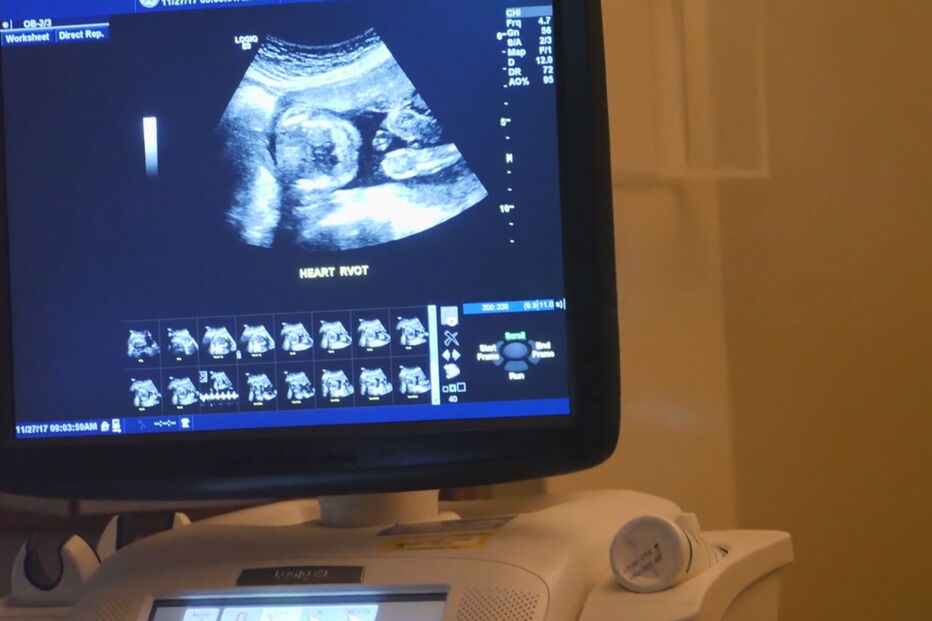

Artur Carvalho, possa continuar a realizar ecografias mesmo que acabe por ser expulso da Ordem dos Médicos. A polémica que envolve o obstetra Artur Carvalho surgiu com a divulgação do caso de um bebé que nasceu com malformações graves que não foram detetadas em nenhuma das várias ecografias realizadas na EcoSado por aquele médico."Nada impede o médico que não notou nada de estranho no exame ao bebé que nasceu sem parte do crânio, sem nariz e sem olhos de continuar a fazer ecografias, mesmo que a Ordem o expulse da profissão", disse o presidente da Associação Portuguesa de Radiologia, Ricardo Sampaio, durante o programa Em Nome da Lei, da Rádio Renascença. Uma questão explicada pelo bastonário da Ordem dos Médicos, Miguel Guimarães, que revelou que a "situação decorre do facto de Portugal não ter uma lei do ato médico, à semelhança do que acontece noutros países".Artur Carvalho, que, entretanto, foi suspenso preventivamente pelo Conselho Disciplinar do Sul da Ordem dos Médicos, tem seis processos em curso neste órgão, e já em 2011 havia sido noticiada uma situação semelhante na Amadora, que motivou também a abertura de um processo disciplinar e uma queixa no Ministério Público, ambos arquivados. O processo mais antigo ainda em aberto no Conselho Disciplinar relativo a este médico obstetra remonta a 2013.